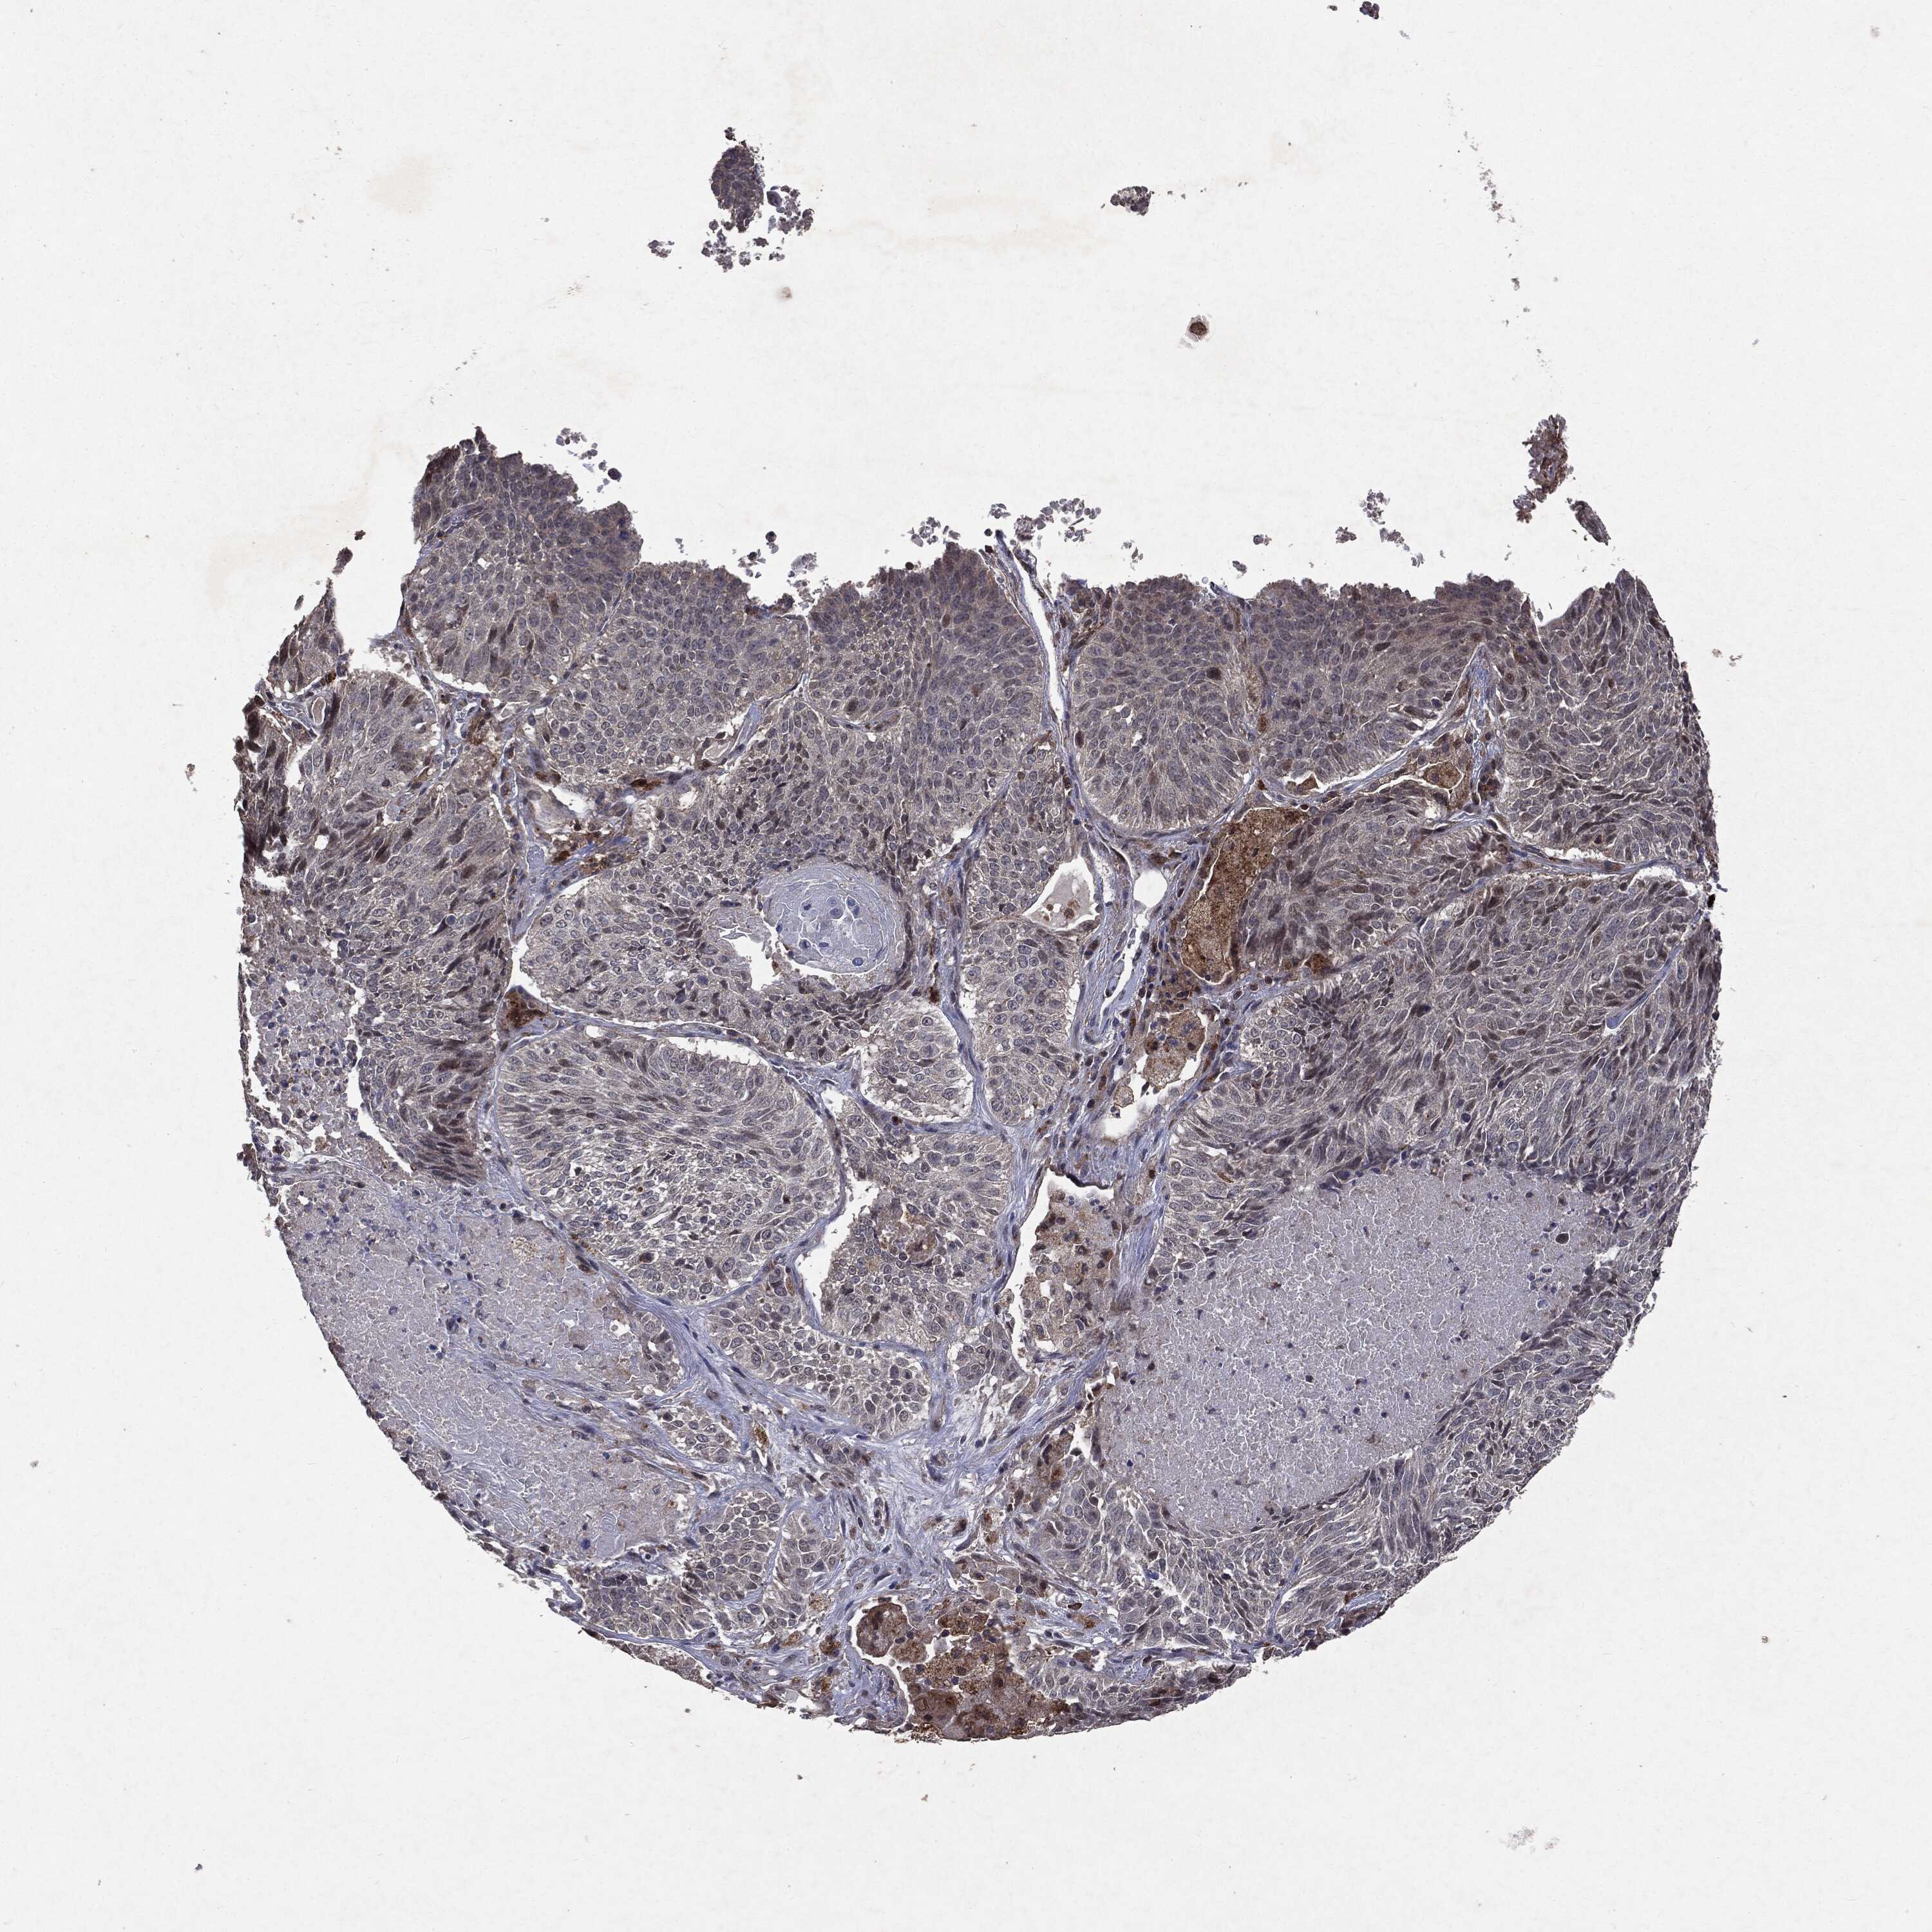

LUNG SQUAMOUS CELL CARCINOMA (TCGA) - Interactive survival scatter ploti

The Survival Scatter plot shows the clinical status (i.e. dead or alive) for all individuals in the patient cohort, based on the same data that underlies the corresponding Kaplan-Meier plots. Patients that are alive at last time for follow-up are shown in blue and patients who have died during the study are shown in red.

The x-axis shows the expression levels (FPKM) of the investigated gene in the tumor tissue at the time of diagnosis. The y-axis shows the follow-up time after diagnosis (years). Both axes are complimented with kernel density curves demonstrating the data density over the axes. The top density plot shows the expression levels (FPKM) distribution among dead (red) and alive patients (blue). The right density plot shows the data density of the survived years of dead patients with high and low expression levels respectively, stratified using the cutoff indicated by the vertical dashed line through the Survival Scatter plot. This cutoff is automatically defined based on the FPKM cutoff that minimizes the p-score. The cutoff can be changed by dragging the vertical line or by entering a cutoff value in the square labeled "Current cut-off".

Under the Survival Scatter plot the p-score landscape (black curve; left axis) is shown together with dead median separation (red curve; right axis). Dead median separation is the difference in median mRNA expression between patients who have died with high and low expression, respectively. It is calculated as follows: median FPKM expression of dead patients with high expression - median FPKM expression of dead patients with low expression. This is intended to aid the user in visually exploring custom cutoffs and the associated p-scores and dead median separation.

Individual patient data is displayed and can be filtered by clicking on one or more of the category buttons on the top of the page. Categories describing expression level and patient information include: high, low, alive, dead, female, male and tumor stages. The scale of the x-axis can be toggled between linear and log-scale by clicking on the "x log" button. Mouse-over function shows TCGA ID, patient information and mRNA expression (FPKM) for each patient.

& Survival analysisi

Kaplan-Meier plots summarize results from analysis of correlation between mRNA expression level and patient survival. Patients were divided based on level of expression into one of the two groups "low" (under cut off) or "high" (over cut off). X-axis shows time for survival (years) and y-axis shows the probability of survival, where 1.0 corresponds to 100 percent.

PTEN is not prognostic in Lung Squamous Cell Carcinoma (TCGA)

Best expression cut offi

Based on the FPKM value of each gene, patients were classified into two groups and association between prognosis (survival) and gene expression (FPKM) was examined. The best expression cut-off refers the FPKM value that yields maximal difference with regard to survival between the two groups at the lowest log-rank P-value. Best expression cut-off was selected based on survival analysis .

When clicking on this number, the vertical dashed line indicating cut-off, the interactive survival plot, and the Kaplan-Meier curve will be adjusted to show results based on the best expression cut-off.

: 14.34

P scorei

Log-rank P value for Kaplan-Meier plot showing results from analysis of correlation between mRNA expression level and patient survival.

N/A

TCGA RNA samplesi

RNA-seq data is reported as average FPKM (number Fragments Per Kilobase of exon per Million reads), generated by the The Cancer Genome Atlas (TCGA) .

Normal distribution across the dataset is visualized with box plots, shown as median and 25th and 75th percentiles. Points are displayed as outliers if they are above or below 1.5 times the interquartile range. FPKM values of the individual samples are presented next to the box plot.

Average pTPM 15.1

Number of samples 489